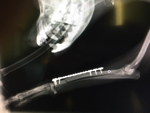

超がつく小ささの前肢の骨折です。

写真だと拡大しているので分かりづらいですが、体重がなんと1kg!両手のひらに乗る大きさで、ネジを打ち込む骨の幅が3.1mmしかありません。5円玉の真ん中の穴ですら4.8mmくらいあります。ちょうど100円玉2枚重ねた厚さと同じくらいです。

現在使用できるロッキングプレート&ネジの最小の物でギリギリです。

関節に近いところが折れているため大変です。

こちらの症例は2度目の骨折です。それも2回目の骨折でプレートがうまくはまっていなかったので今回ロッキングプレートにてやり直しました。

数ヶ月後にはほぼくっついています。